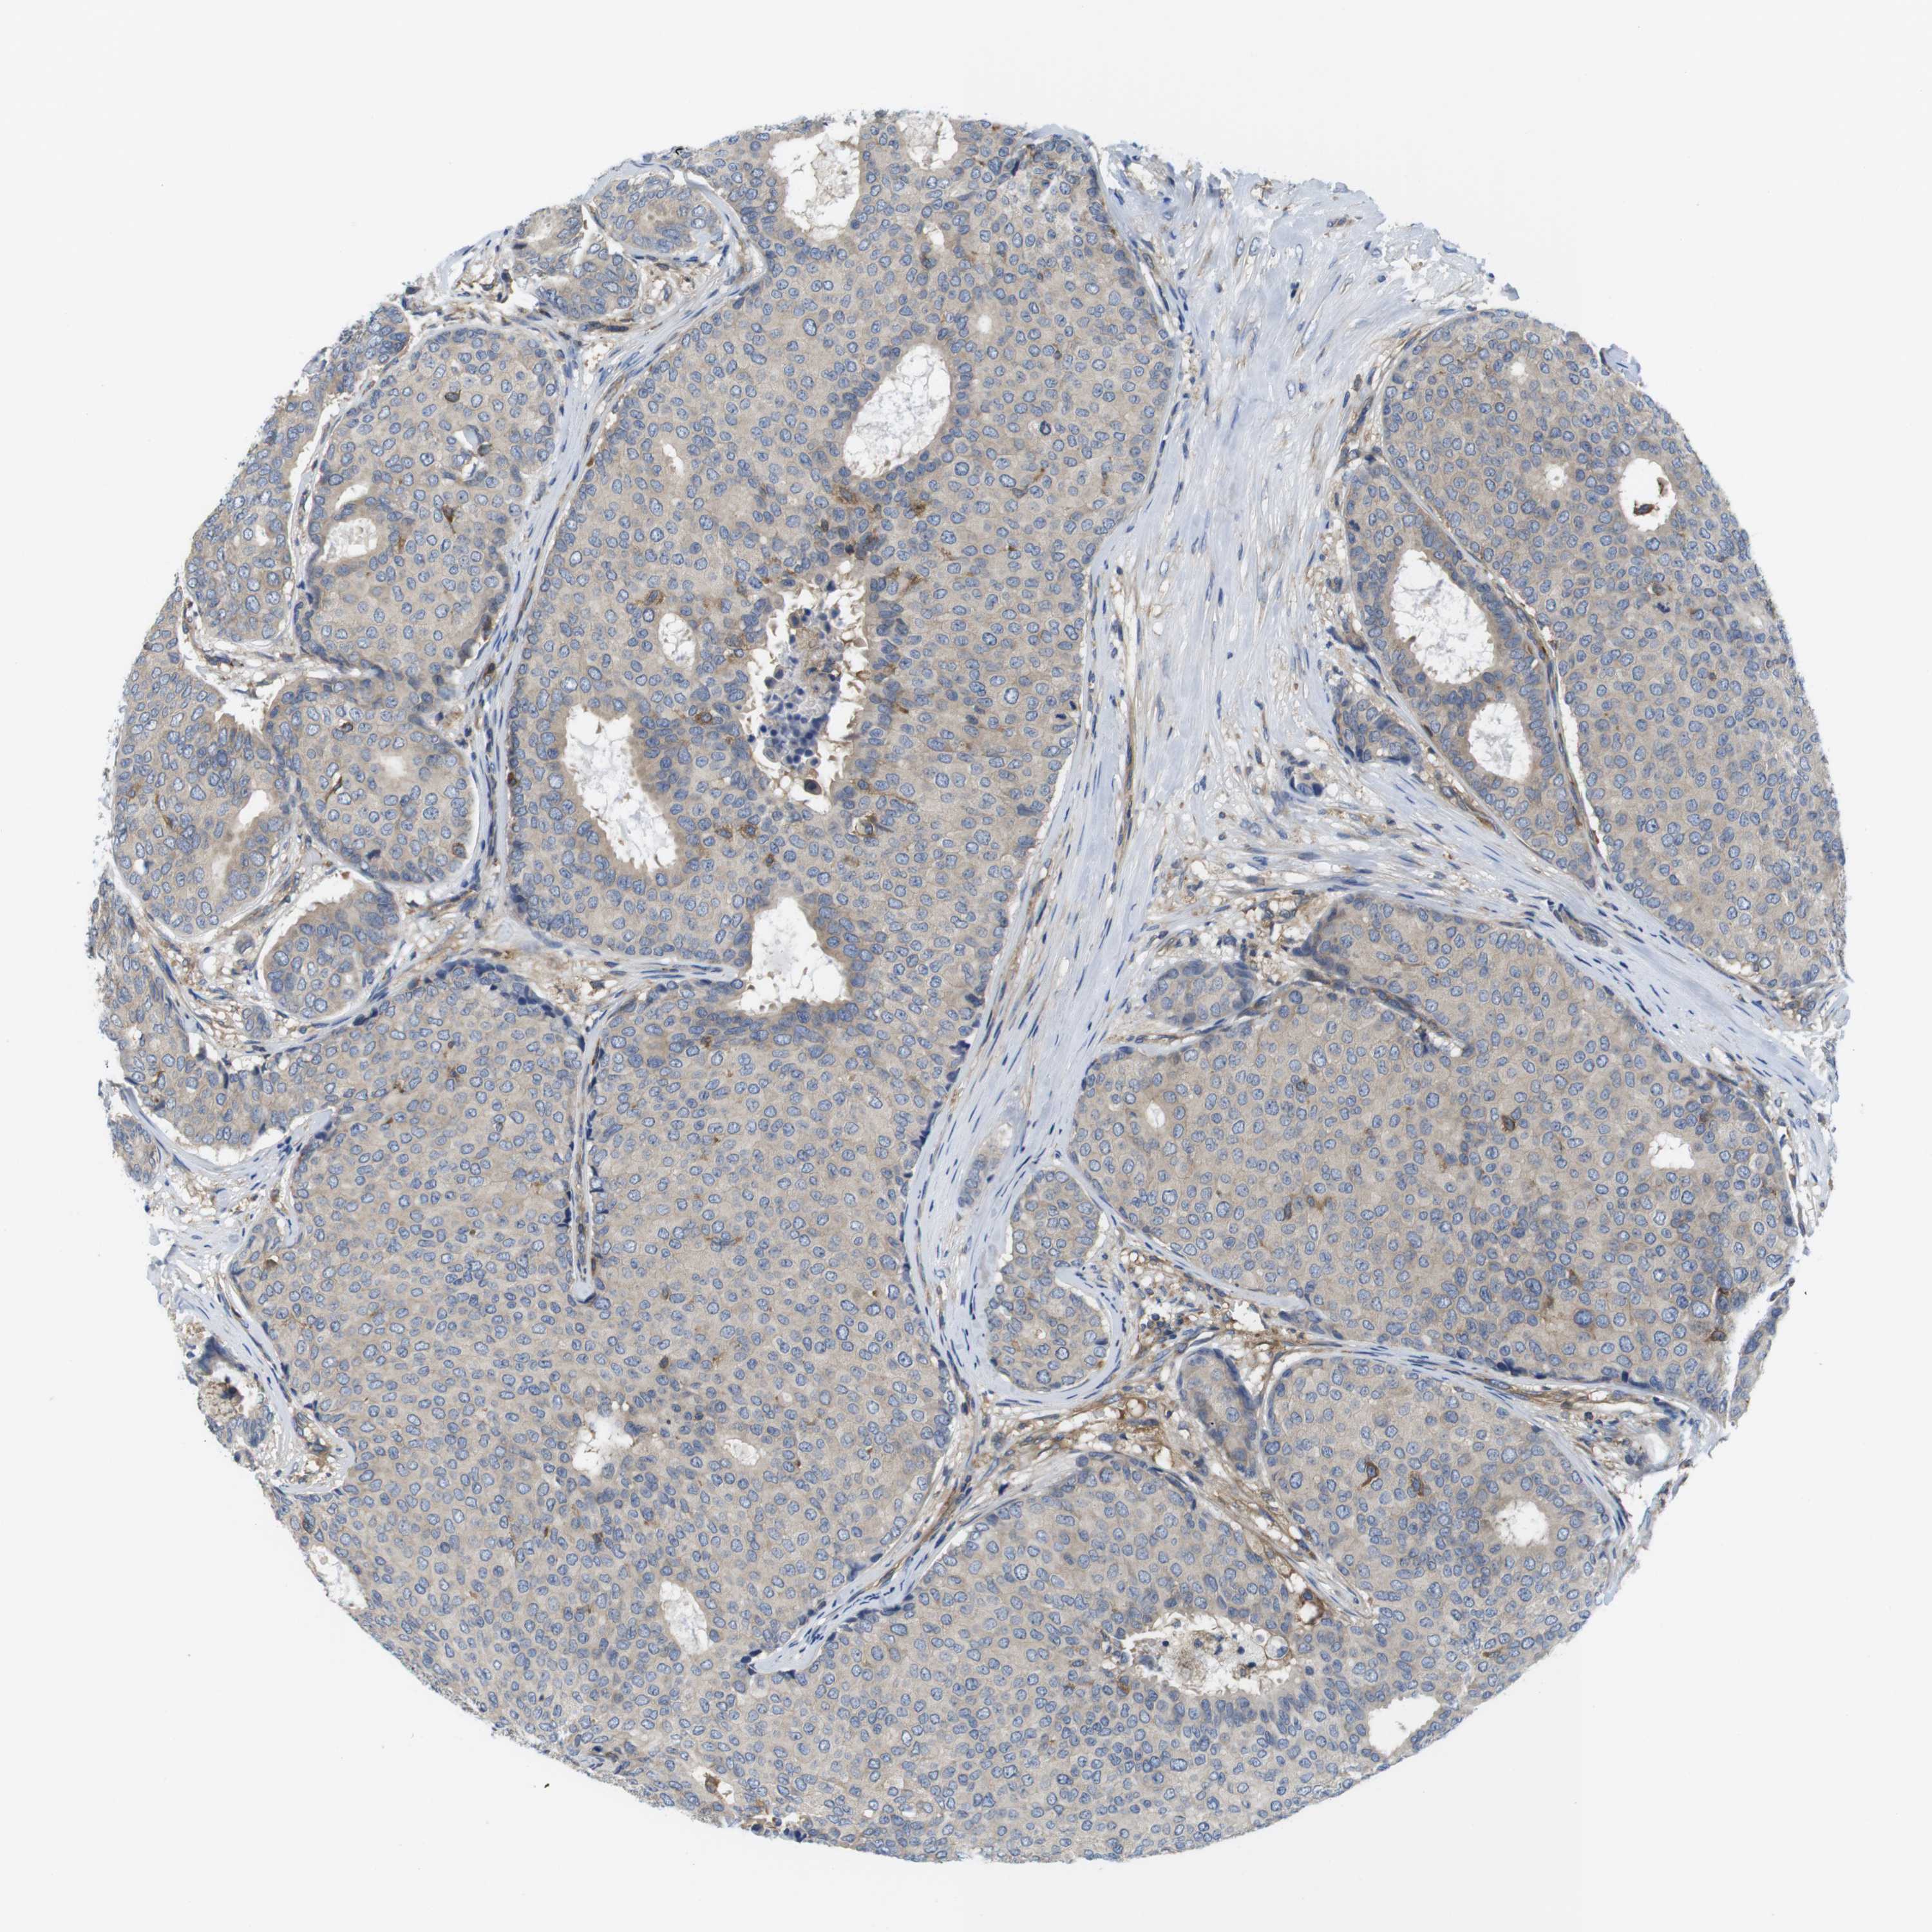

CANCER BREAST CANCER Show tissue menu

BRCA TCGA BRCA VALIDATION PROTEIN EXPRESSION